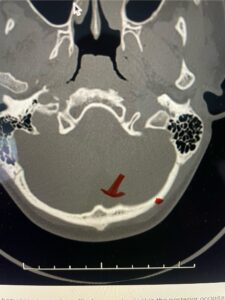

(Fig. 1). This bone is quite thick, about 15 mm (Figs. 2a and b). Most modern plate systems utilize three midline keel screws with the option to place within a 2 cm lateral fixation point. This plate is connected to sometimes tricky-to-bend rods and connected to screw fixation points in the cervical spine (Fig. 3). Bone graft material extends from skull to cervical spine.

Fig. 2b: Axial CT scan of the brain demonstrating the thickness of the midline keel (red arrow) compared to the more lateral subocciput (red dot) making the keel ideal place for screw fixation